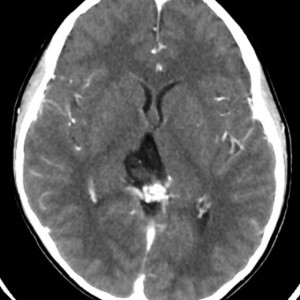

CTです

左のCTでは低密度の松果体腫瘍とまばらな石灰化がみられます。右の造影CTでは,腫瘍のごく一部が増強されます。 この時点で,低吸収で石灰化があるので類皮のう胞 dermoid cystを強く疑います。dermoid cystを主体とする混合性胚細胞腫瘍 mixed germ cell tumorも候補です。あるとすれば,germinomaかteratomaです。